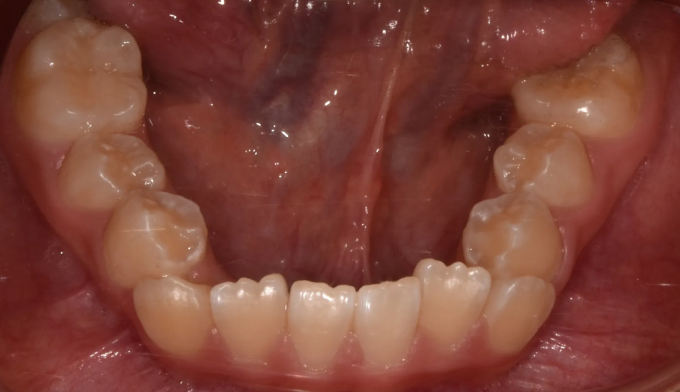

너무 늦은나이에 교정치과를 찾아서 아쉬운 경우입니다.

너무 좁은 위턱 공간으로 인해 치아의 맹출 순서가 어긋나버렸습니다.

송곳니가 원래 나와야 할 공간이 없다보니 작은 어금니 위치로 이동해서 맹출하고 있습니다. 이를 치아 전위라고 합니다.

이와 더불어 좁은 위턱 악궁은 얼굴 전체의 비대칭을 유발하고 있고, 아래턱의 과성장은 주걱턱 경향까지 보이고 있습니다.